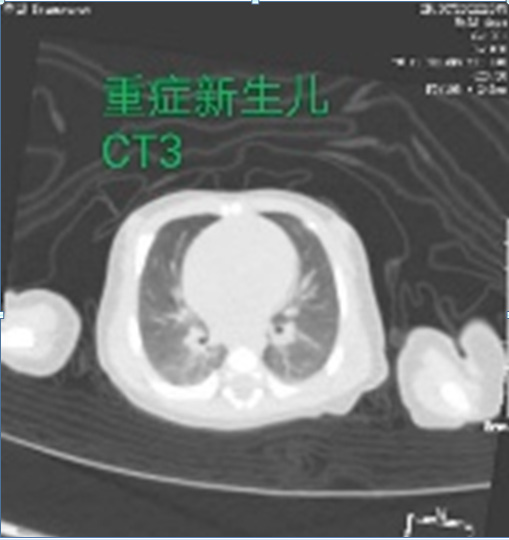

Computer tomography showed local thickening of double lung texture, small patch density increased shadows. A fuzzy edge was found. Chest CT reviewed on March 1 showed, that the lung film was more clearly absorbed than before. After admission, the child was placed in the isolation ward for treatment and have been given a warm box insulation. The newborn had nasal catheter application of oxygen, interferon injection by oral cavity and ambroxole at the same time. The heart rate was closely monitored. Respiration, blood pressure, electrolyte were also closely monitored. Furosemide was given as diuretic, cefoperazone was given. Sedation, heart strengthening, diuretic, fluid limitation, circulation improvements were initiated. IN the next days, the child’s body temperature was normal, no cough, no dyspnea, good nursing, normal defecation and urination. Further two time nucleic acid tests were negative and the condition of the newborn was significantly improved. They were followed up for two weeks after discharge. Finally, the baby recovered normal, and the spirit and aspect was finally very good. No rise of temperature of fever was found in course.